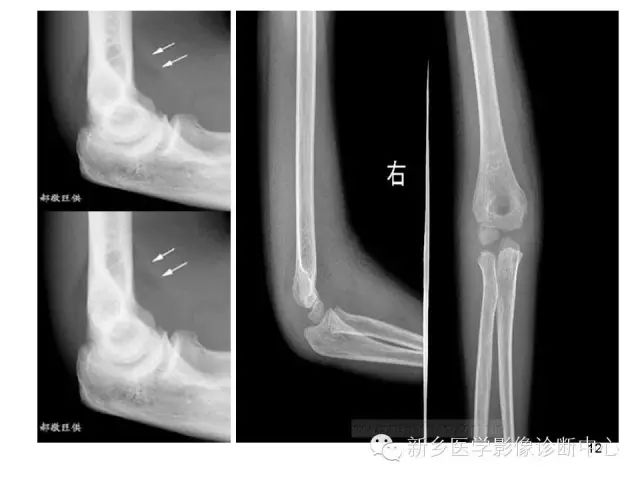

1.在标准的肘关节侧位片上,肱骨前缘可见一条形透亮影,这是正常附着在关节囊的脂肪组织。

2.而肱骨后缘的脂肪组织由于附着在髁间窝内而不可见。

正常肘部侧位片,肘关节囊前后都有脂肪组织,充填于鹰嘴窝、喙突窝和桡骨头窝内,侧位X线片掌侧见长条状低密度脂肪影,覆于骨皮质,下端至喙突窝的下缘,背侧脂肪影不能显示。

正常鹰嘴窝脂肪在肘关节X线侧位片上不显影,当肘关节内有积液达5-10ml以上,可将脂肪组织推移并显影,称“鹰嘴窝脂肪垫显影移位征”。肘关节造影证实,关节囊内积液可使肘关节外脂肪推移,推移程度与积液量密切相关。关节囊内大量积液时,关节囊膨胀呈球状,屈肘90°摄侧位片,掌背侧脂肪影均离开骨皮质而呈“八字胡”样改变。伸肘时脂肪影与皮质靠近,说明肘关节处脂肪影改变完全受关节内液体移动所影响。

八字征(脂肪垫征):

骨折损伤周围组织,引起关节腔的积血。正常的脂肪组织向关节囊的外侧及上方移位,在平片上形成了八字征。

1.八字征在肘关节骨折的诊断中具有决定性的作用

2.通常八字征阴性而又存在骨折的情况是不存在的。

3.如果八字征阳性,却没能够发现骨折,考虑是否存在隐匿性骨折,同样需要按未移位骨折来固定处理。

4.肘关节X光片无骨折线,不能说“肘关节骨关节无异常”,脂肪垫征对小孩的损伤检查有帮助。

脂肪垫征见于髁上和侧髁骨折。